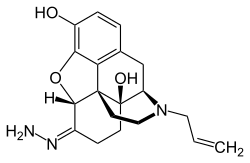

Several semi-synthetic opioids were developed in Germany in the 1910s. The first, oxymorphone, was synthesized from thebaine, an opioid alkaloid in opium poppies, in 1914.[228] Next, Martin Freund and Edmund Speyer developed oxycodone, also from thebaine, at the University of Frankfurt in 1916.[229] In 1920, hydrocodone was prepared by Carl Mannich and Helene Löwenheim, deriving it from codeine. In 1924, hydromorphone was synthesized by adding hydrogen to morphine. Etorphine was synthesized in 1960, from the oripavine in opium poppy straw. Buprenorphine was discovered in 1972.[228]